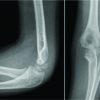

A 34-year-old female presented with dull low back pain radiating to bilateral lower limb and paresthesias in the lower limb of 2 years duration. It was associated with episodic palpitation, perspiration, and occasional headache for 2 years. Medical history was positive for two episodes of hypertensive urgency which required inpatient admission and management. However, at no time, further evaluation was carried out to investigate the etiology for the hypertension. On general examination, she was a female in her early 30s averagely build and nourished. Vitals were within normal limits with the exception of few episodes of hypertension where the BP reached maximum of 220/140 mmHg. Low back pain was not associated with any spinal tenderness and neurological examination was unremarkable. Laboratory investigations revealed that plasma-free normetanephrine was 4555pg/ml (Normal= 0–196). Plain radiographs of the lumbosacral spine showed scalloping of the anterior border of L1 vertebra and degenerative changes lower down at L4-L5 (Fig. 1). Magnetic resonance imaging (MRI) of the lumbar spine revealed heterogeneously enhancing retroperitoneal lesion at L1 with areas of necrosis (Fig. 2-4). Both adrenal glands were unremarkable. Computed tomography (CT) abdomen and pelvis were suggestive of hyperenhancing lobulated mass measuring 29× 49 mm axially closely abutting abdominal aorta for more than 90° but <180° with loss of intervening fat planes at L1 with scalloping and anterior destruction of L1 vertebral body. Positronemission tomography (PET) scan was suggestive of metabolically active lesion seen at L1 and L2 vertebra (Fig. 5). Scintigraphic evidence of metaiodobenzylguanidine (MIBG) avid mass in upper abdomen suggesting paraganglioma was found on iodine-123-MIBG scan (Fig. 6). The patient required pre-operative optimization of blood pressure with the combination of alpha-blockers and beta-blockers in optimum dosage before surgical resection. The patient underwent angioembolization before the surgery in view of high vascularity to reduce the intraoperative blood loss. Bilateral feeders from lumbar arteries were embolized with 100–200µ particles. Surgical approach was planned as a staged procedure. In the first stage in prone position under general anesthesia, a midline posterior approach was used. Pedicular screw instrumentation (except at L1) and fusion were performed from D11 to L3 (Fig. 7). In the second stage, the patient underwent excision of tumor mass with L1 corpectomy and anterior reconstruction with an expandable titanium cage and tricortical onlay graft by a retroperitoneal approach in the right lateral position (Fig. 8-10). The graft was harvested from the left iliac crest. Intraoperatively, there were fluctuations of blood pressure during tumor removal which was handled well with inotropic support. Histopathology report was suggestive of cells in nests, “Zellballen”(ball of cells) pattern. On immunohistochemistry, tumor cells were positive for chromogranin A, S-100, Cyclin-D1, and weakly positive for synaptophysin. Nuclei showed atypia; however, mitotic activity was absent. The patient was immobilized for 3 weeks in bed following which she was mobilized with a Taylor’s brace. The patient remained neurologically intact following the second stage of surgery and is at present asymptomatic 8 months following the surgery with no complaints of backache, palpitations, or hypertension.